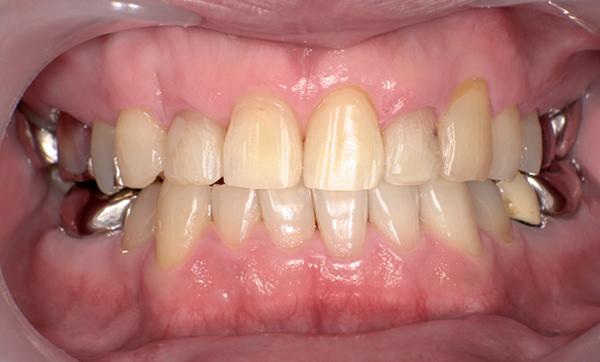

抜歯を伴った部分矯正の症例

当院は基本的には抜歯せずに、ディスキング(歯の横の面をエナメル質の範囲内で多少削る)にて歯列矯正しています。

ただし、部分矯正でも必要であれば抜歯を行なって治療を行うこともございます。

また、歯を並べるスペースが元々確保できる場合は、抜歯もディスキングも行わずに治療します。

| Before | After |

|---|---|

|

症例詳細:上顎の部分矯正、治療期間:7ヶ月、矯正装置1本:3.5万円+tax、リスク:後戻りの可能性